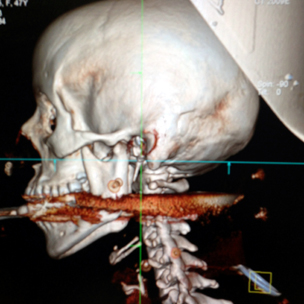

برازيليا: قال أطباء إن إمرأة برازيلية نجت من الموت بأعجوبة بعد أن أصيبت في فمها برمح من التي تستخدم في صيد الحيتان، وذلك في حادث غريب.

وقال جراح الأعصاب آلان دا كوستا حسب ما جاء في هيئة الإذاعة البريطانية إن المصابة اليسانجيلا بوربوريما روزا البالغة من العمر 28 عاما كانت قد هلكت لا محالة لو كان الرمح قد تحرك بمسافة سنتمتر واحد.

ودخل الرمح الذي يستخدمه زوجها في الصيد فمها واستقر قرب حبلها الشوكي.

وقال الجراح دا كوستا "لم أر حالة كهذه من قبل، فعنصر الغرابة في هذه الحالة يكمن في أن رأس الرمح استقر بين القناة الشوكية الأمامية والقناة النخاعية (في العمود الفقري). فلو كان مكان استقراره قد انحرف بمقدار سنتمتر واحد من احدى الجهات لكانت اصيبت بالشلل، اما لو كان مكان استقراره قد انحرف سنتمترا واحدا الى الجهة الأخرى لضرب أحد الشرايين المهمة ولكانت قد توفيت جراء النزف."